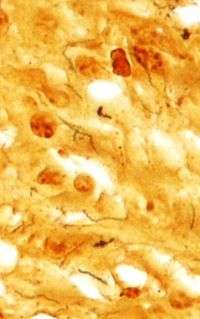

Treponema pallidum is a spirochaete bacterium with subspecies that cause treponemal diseases such as syphilis, bejel, pinta, and yaws. The treponemes have a cytoplasmic and an outer membrane. Using light microscopy, treponemes are only visible using dark field illumination. They are Gram negative, but some regard them too thin to be Gram stained.

This bacterium can be detected with special stains, such as the Dieterle stain. T. pallidum is also detected by serology, including nontreponemal VDRL, rapid plasma reagin, and treponemal antibody tests (FTA-ABS), T. pallidum immobilization reaction, and syphilis TPHA test).[2]